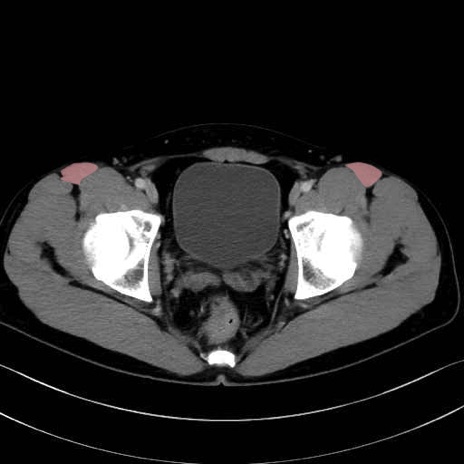

大殿筋 (Gluteus maximus)

大腿筋膜張筋 (Tensor fasciae latae)

縫工筋 (Sartorius)